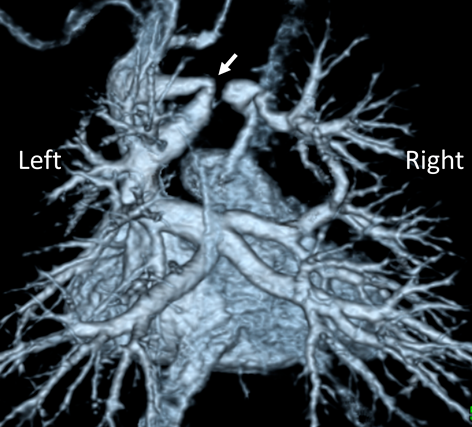

総肺静脈還流異常を合併した垂直静脈狭窄に対するステント留置中のバルーンエントラップメントEntrapment of a Balloon Catheter during Stent Implantation for Vertical Venous Stenosis in Two Neonates with Single Ventricle and Total Anomalous Pulmonary Venous Connection